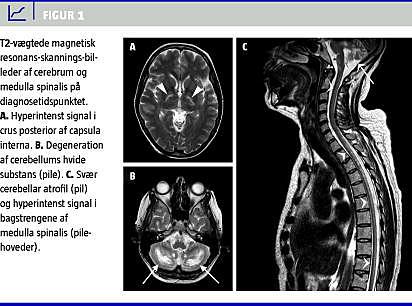

En ny MR-skanning af hjernen og rygmarven foretaget et år efter den forrige (Figur 1 ) afslørede hyperintenst signal på T2-vægtede billeder i capsula interna og pyramidebanen i hjernestammen (Figur 1A + B), degeneration af cerebellums hvide substans (Figur 1B) og svær cerebellar atrofi (Figur 1C). På MR-skanningen af rygmarven påviste man diffust hyperintenst T2-signal langs bagstrengene (Figur 1C). Baseret på de kliniske og billedmæssige fund var der mistanke om CTX, og en genetisk analyse afslørede to kendte mutationer på CYP27A1 : c.1184+1G>A og c.1213C>T. I lighed hermed viste biokemiske analyser et massivt forhøjet 7-alfa-hydroxykolesterolniveau på 1.286 ng/ml (normalværdi: < 50 ng/ml), og der blev påbegyndt behandling med CDCA (250 mg × 3).